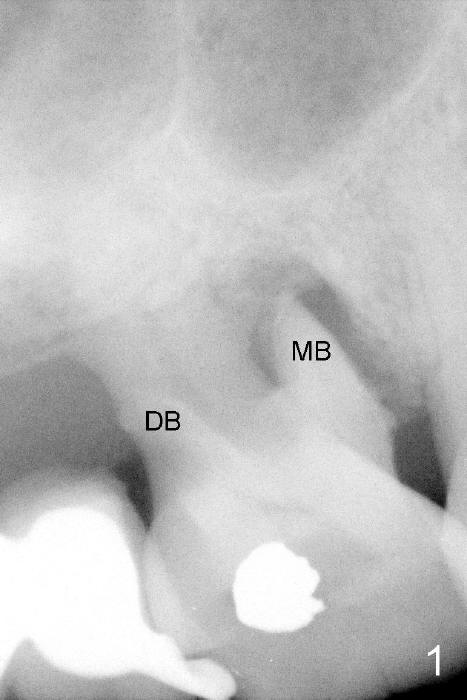

Lack of bony support and soft tissue coverage appear to be an obstacle to immediate implant. Two cases are presented. The first one is my first attempted immediate implant patient (Fig.1-3), a 54-year-old lady. She is extremely apprehensive. The upper right first molar has severe perio-endo disease. There is no bone around the buccal roots (MB, DB in Fig.1). The tooth is non salvageable and is treated the best with an immediate implant. When the tooth is extracted, the large buccal gingival defects (Fig.2 MB, DB) and sinus perforation (Fig.3) through the palatal socket (Fig.2 *) are apparent contraindications to immediate implant. Amazingly, the gingiva heals rapidly post extraction. An implant is placed 1 month later.